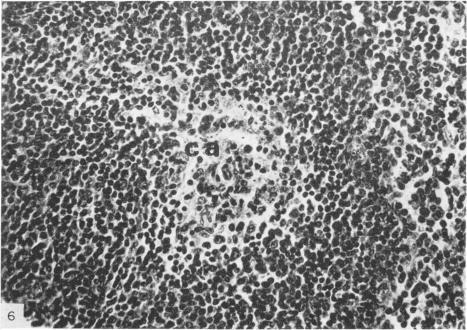

The lymph nodes, spleens and Peyer's patches from seven mutant mice with agenesis of the thymus were compared with similar tissues from eight phenotypically normal littermate controls. In all lymph nodes examined from the mice the thymus-dependent areas were virtually `empty' of lymphocytes. In the corresponding areas in the spleen and Peyer's patches the numbers of lymphocytes were also significantly reduced. The mice are potentially important as experimental tools in delineating the role of the thymus in the development of the lymphoid system, and as an experimental model of thymic alymphoplasia in the human.

将7只胸腺发育不全的突变小鼠的淋巴结、脾脏和派伊尔氏结与8只表型正常的同窝对照小鼠的相似组织进行了比较。在检查的所有突变小鼠的淋巴结中,胸腺依赖区几乎没有淋巴细胞。在脾脏和派伊尔氏结的相应区域,淋巴细胞数量也显著减少。这些突变小鼠作为实验工具在阐明胸腺在淋巴系统发育中的作用方面可能具有重要意义,并且可作为人类胸腺淋巴细胞发育不全的实验模型。